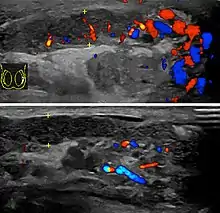

In those who are young and sexually active, gonorrhea and chlamydia are frequently the underlying cause.[1] In older males and men who practice insertive anal sex, enteric bacteria are a common cause.[1] Diagnosis is typically based on symptoms.[1] Conditions that may result in similar symptoms include testicular torsion, inguinal hernia, and testicular cancer.[1] Ultrasound can be useful if the diagnosis is unclear.[1]

Diagnosis is typically based on symptoms.[1] Conditions that may result in similar symptoms include testicular torsion, inguinal hernia, and testicular cancer.[1] Ultrasound can be useful if the diagnosis is unclear.[1]

Epididymitis usually has a gradual onset. Typical findings are redness, warmth and swelling of the scrotum, with tenderness behind the testicle, away from the middle (this is the normal position of the epididymis relative to the testicle). The cremasteric reflex (elevation of the testicle in response to stroking the upper inner thigh) remains normal.[1] This is a useful sign to distinguish it from testicular torsion. If there is pain relieved by elevation of the testicle, this is called Prehn's sign, which is, however, non-specific and is not useful for diagnosis.[13] Before the advent of sophisticated medical imaging techniques, surgical exploration was the standard of care. Today, Doppler ultrasound is a common test: it can demonstrate areas of blood flow and can distinguish clearly between epididymitis and torsion. However, as torsion and other sources of testicular pain can often be determined by palpation alone, some studies have suggested that the only real benefit of an ultrasound is to assure the person that they do not have testicular cancer.[14]: p.237 Nuclear testicular blood flow testing is rarely used.